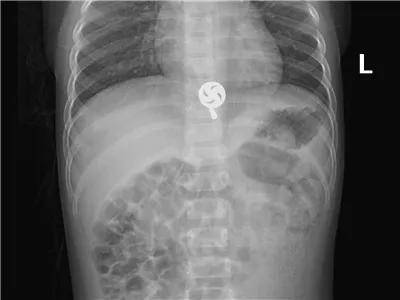

4岁·金属坠

入院1小时前误服5角硬币大小的金属吊坠。